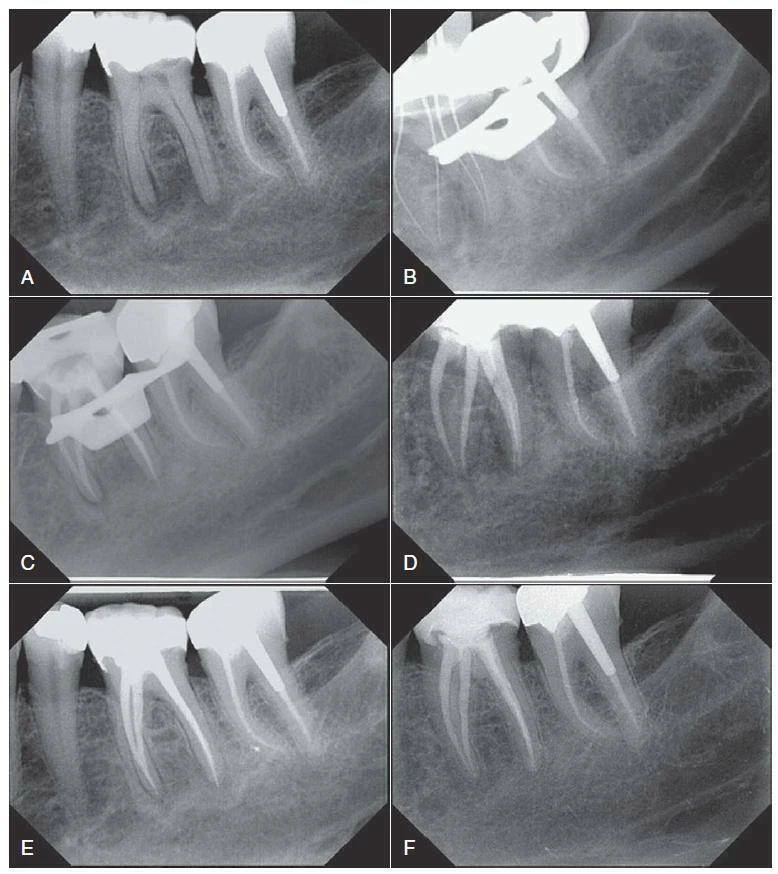

Hình 9.1 Tác động của điều trị tuỷ trên răng hàm – hàm dưới. A – Hình ảnh phim chụp trước khi điều trị của răng #19 cho thấy tổn thương thấu quang ở phía xa và phía gần của phần chóp răng. B – Hình ảnh phim chụp kiểm soát chiều dài làm việc cho thấy hai ống tuỷ phân biệt ở chân gần và hai ống tuỷ gần như nhập vào nhau ở chân xa. C – Hình ảnh phim chụp sau tạo hình hệ thống ống tuỷ với file nickel- titanium và trám bít bằng gutta-percha hơ nóng. D – Hình ảnh phim chụp tái khám sau 6 tháng răng #19 với phục hồilà chụp sứ; tái tạo xương gần chóp có thể quan sát thấy. E – Hình ảnh phim chụp tái khám sau 1 năm cho thấy sự liền thương tiếp tục ở vùng cận chóp. F – Hình ảnh phim chụp tái khám sau 5 năm, răng không chỉ hồi phục ở vùng cận chóp mà còn đáp ứng đủ chức năng và không có triệu chứng trên lâm sàng.